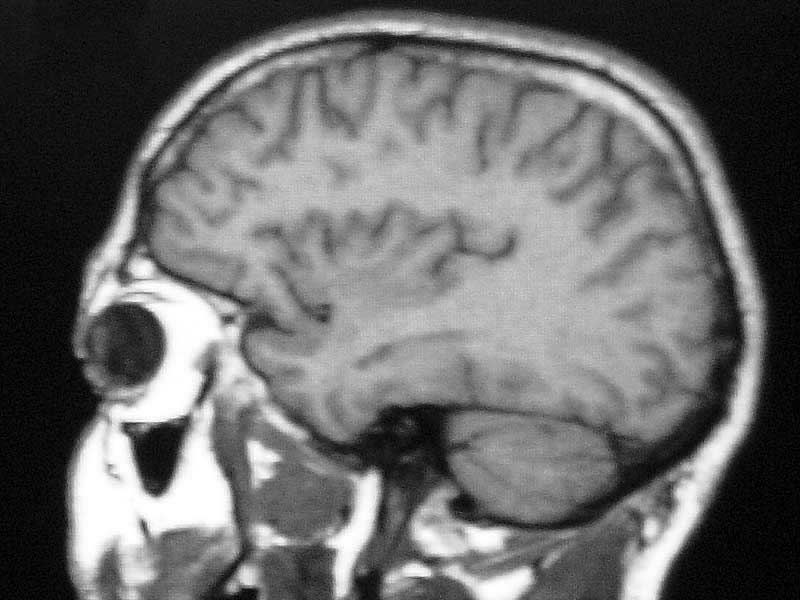

Up one "You need your head examining."